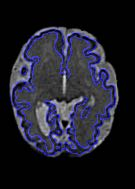

Fetal cortical plate segmentation is essential in quantitative analysis of fetal brain maturation and cortical folding. Manual segmentation of the cortical plate, or manual refinement of automatic segmentations is tedious and time-consuming. Automatic segmentation of the cortical plate, on the other hand, is challenged by the relatively low resolution of the reconstructed fetal brain MRI scans compared to the thin structure of the cortical plate, partial voluming, and the wide range of variations in the morphology of the cortical plate as the brain matures during gestation. To reduce the burden of manual refinement of segmentations, we have developed a new and powerful deep learning segmentation method. Our method exploits new deep attentive modules with mixed kernel convolutions within a fully convolutional neural network architecture that utilizes deep supervision and residual connections. We evaluated our method quantitatively based on several performance measures and expert evaluations. Results show that our method outperforms several state-of-the-art deep models for segmentation, as well as a state-of-the-art multi-atlas segmentation technique. We achieved average Dice similarity coefficient of 0.87, average Hausdorff distance of 0.96 mm, and average symmetric surface difference of 0.28 mm on reconstructed fetal brain MRI scans of fetuses scanned in the gestational age range of 16 to 39 weeks. With a computation time of less than 1 minute per fetal brain, our method can facilitate and accelerate large-scale studies on normal and altered fetal brain cortical maturation and folding.